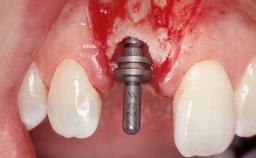

Immediate Flapless Placement of an Implant in a Maxillary Left Central Incisor Site

A 42-year-old female patient was referred to our clinic at the School of Dentistry of the University of São Paulo in November 2004, presenting a deficient restoration in the upper left central incisor. The clinical examination revealed no gingival retraction or any signs of gingival inflammation and, therefore, previous periodontal treatment was not considered. The patient presented a high lip line at full smile and a thin tissue biotype. This combination characterized a high-risk situation from an anatomic point of view, which required careful preoperative planning and cautious surgical execution.

Type of Implants One-Piece

Placement Protocol Immediate implant placement

Tooth Site Maxillary incisor or canine

Socket Morphology Single-root socket

Socket Integrity Sufficient, with intact bone walls

Bone Volume Sufficient, with intact walls